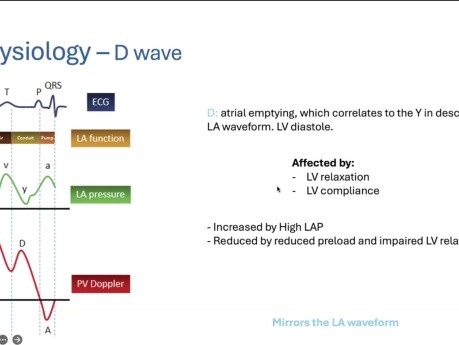

Echokardiograficzna ocena żył płucnych

Prelegent: Basma Mohammed, PGY-5, University of Toronto. Cele: 1. Anatomia żył płucnych. 2. Fizjologia żył płucnych. 3. Wpływ różnych patologii na doppler żył płucnych.